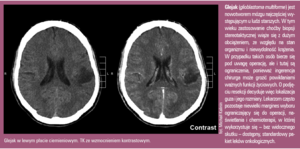

Zrozumieć i osaczyć glejaka

Naukowcy z Poznania pracują nad oryginalną, nowatorską terapią, która szybko przybliża nas do pokonania najgroźniejszego raka mózgu – pierwotnego glejaka wielopostaciowego

Trudny przeciwnik

Do pełnego obrazu nowotworu trzeba dopisać wiele innych cech sytuujących go na czele listy najgroźniejszych. Do nich należy zdolność jednej komórki do skolonizowania otoczenia przez naciekanie bez widocznych granic oraz tworzenie nowych, małych guzków upodabniających się do izolowanych wysepek na wodach oceanu. Glejak wykazuje przy tym niezwykłą dynamikę wzrostu także po chirurgicznym wycięciu, gdy odrasta w błyskawicznym tempie, w dodatku ze zdwojoną złośliwością. Jego agresywność przejawia się też w wyjątkowej zdolności do angiogenezy i w braku apoptozy.